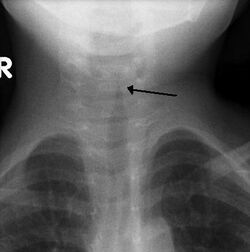

Classic steeple sign indicating croup

Croup (Laryngotracheobronchitis) is a viral infection of the vocal cords typically lasting five to six days. The main symptom is a barking cough and low-grade fever. On an X-ray, croup can be recognized by the "steeple sign", which is a narrowing of the trachea. It most commonly occurs in winter months in children between the ages of 3 months and 5 years. A severe form caused by bacteria is called bacterial tracheitis.[12]